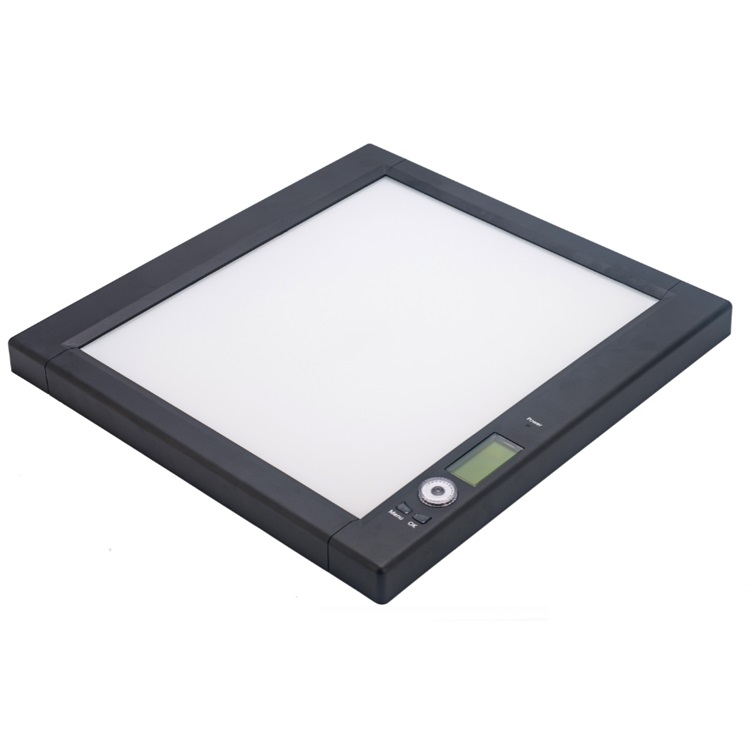

- Type:

- Clinical Examination Aids

- Model Number:

- LEDXV-I

- Size:

- 480*502*38mm

- Average Luminance:

- 0~6000cd/ m2

- Visual Area:

- 360mm*422mm

Negatoscope Dental X-ray Film Viwer LED Price for Sale

1. Full Digital Control

Compared to the analog control, it works more stable, flexible, accuracy, easier to use as well as longer lifespan.

2.Imported Acrylic View Panel

Better light transmission and scattering diffusion, durable, never out of shape or discolored.

3. Super Bright LED Light Source with Quality Lead-frame and Big-size Epitaxial Chips

Side lighting cold light illuminator, high density SMD LED matrix(144 pc/bank), the luminance up to 6000 cd/m2, and uniformity up to 90%, ensured the high brightness and great uniformity, guaranteed the accurate observation.

4. Film Sensor

The panel will light up automatically when film inserted and off when moved away, and the panels in each bank works separately, can avoid the light influence from other panels while observing.

5. PWM Low-Voltage Digital Continuous Dimming System

Luminance can be modulated range from 1% to 100% continuously.

6. LED Constant Current Drive Power

Guaranteed the LED light works consistently, and makes the viewer longer lifespan, energy saving and safety to users.

7. Eye Protective Feature

The color temperature is up to 8000K, no harmful to human eyes, suit for long time observation.

8. Separated Control

Each bank can light up and dimming separately, every bank can be worked as a single viewer.

9. Improved Fixture

Instead of the clip+ball fixture, a new needle roller fixture was adopted, it is more durable and easier to use.

LED-XV Series | Single | Double | Triple | Quadruple |

Size(L×W×H mm) | 480×502×38 | 840×502×38 | 1200×505×38 | 1555×505×25 |

Visual Area(L×W mm) | 360×422 | 720×422 | 1080×422 | 1440×422 |

Power(W) | 30W | 60W | 90W | 120W |

LED Specification&Lifespan | Super Bright SMD LED, 572pcs/bank; CCT ≥ 8000K;Lifespan ≥ 100000 hours | |||

Adaptor | Global Adaptive Power;AC90V-240V ,50/60Hz | |||

View Panel Luminance | PWM Dimming System, can be modulated range from 1% to 100% continuously, 3 inch LCD displayer, average Luminance :0~6000cd/ m2 | |||

Sensor function | The panel will light up automatically when film inserted and off when moved away | |||

≥90% | ||||

Fixture | SS roller oblique compression type Fixture | |||

Installation | ||||

Application Scope | General Film,Digital Film,Breast Mammography Film | |||

Application Condition | ||||

Features | · Full Digital Control · Advanced Ultra Bright LED Light Source with Quality Lead-frame and Big-size Epitaxial Chips · Imported Acrylic View Panel · Eye Protective Feature · PWM Low-Voltage Digital Continuous Dimming System · LED Constant Current Drive Power · Automatic film activation · Improved film clip | |||